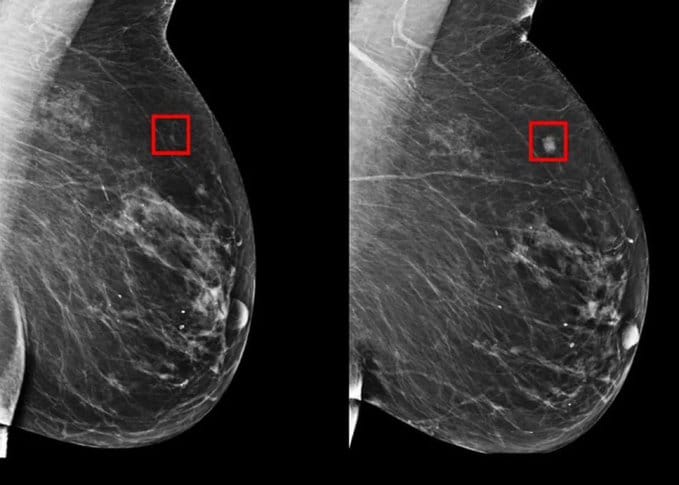

AI-Powered Model Improves Breast Cancer Prediction

Image: Sciene.org

A recent study published in Science introduces Mirai, a mammography-based deep learning model designed to predict breast cancer risk up to five years before it emerges. Developed to improve early detection and reduce screening harm, Mirai was trained on data from Massachusetts General Hospital (MGH) and tested on datasets from MGH, Karolinska University Hospital in Sweden, and Chang Gung Memorial Hospital (CGMH) in Taiwan. Mirai achieved C-indices of 0.76, 0.81, and 0.79, respectively, surpassing the Tyrer-Cuzick model and prior deep learning models. It accurately identified 41.5% of high-risk patients who would develop cancer within five years, compared to 36.1% by Hybrid DL and 22.9% by Tyrer-Cuzick. These results underscore Mirai's potential to refine clinical workflows and enhance targeted screening strategies, promising earlier detection and better patient outcomes.